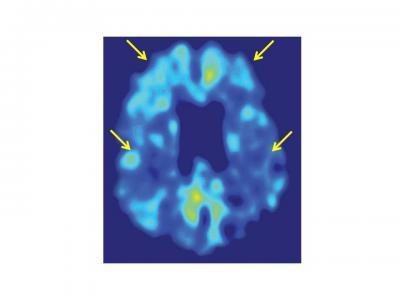

An FDDNP brain scan of an individual with mild cognitive impairment illustrates the parietal and frontal regions of the brain (see arrows) that have significant relationships to cognitive function. The lateral temporal lobe was another significant region, but is not included in this brain section.

(Photo Credit: UCLA)